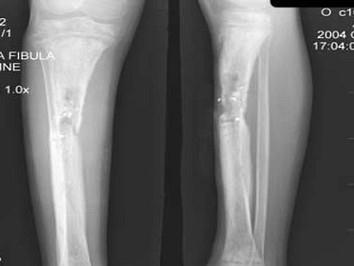

问题 12岁,女性患者,因右小腿肿胀,疼痛,发热3月余,摄片如图所示,下列征象那项是错误的: ( )

选项 A、可见软组织肿块 B、以上都不正确 C、骨质增生硬化 D、骨膜呈层状增生不明显 E、骨质呈溶骨性破坏

答案 A